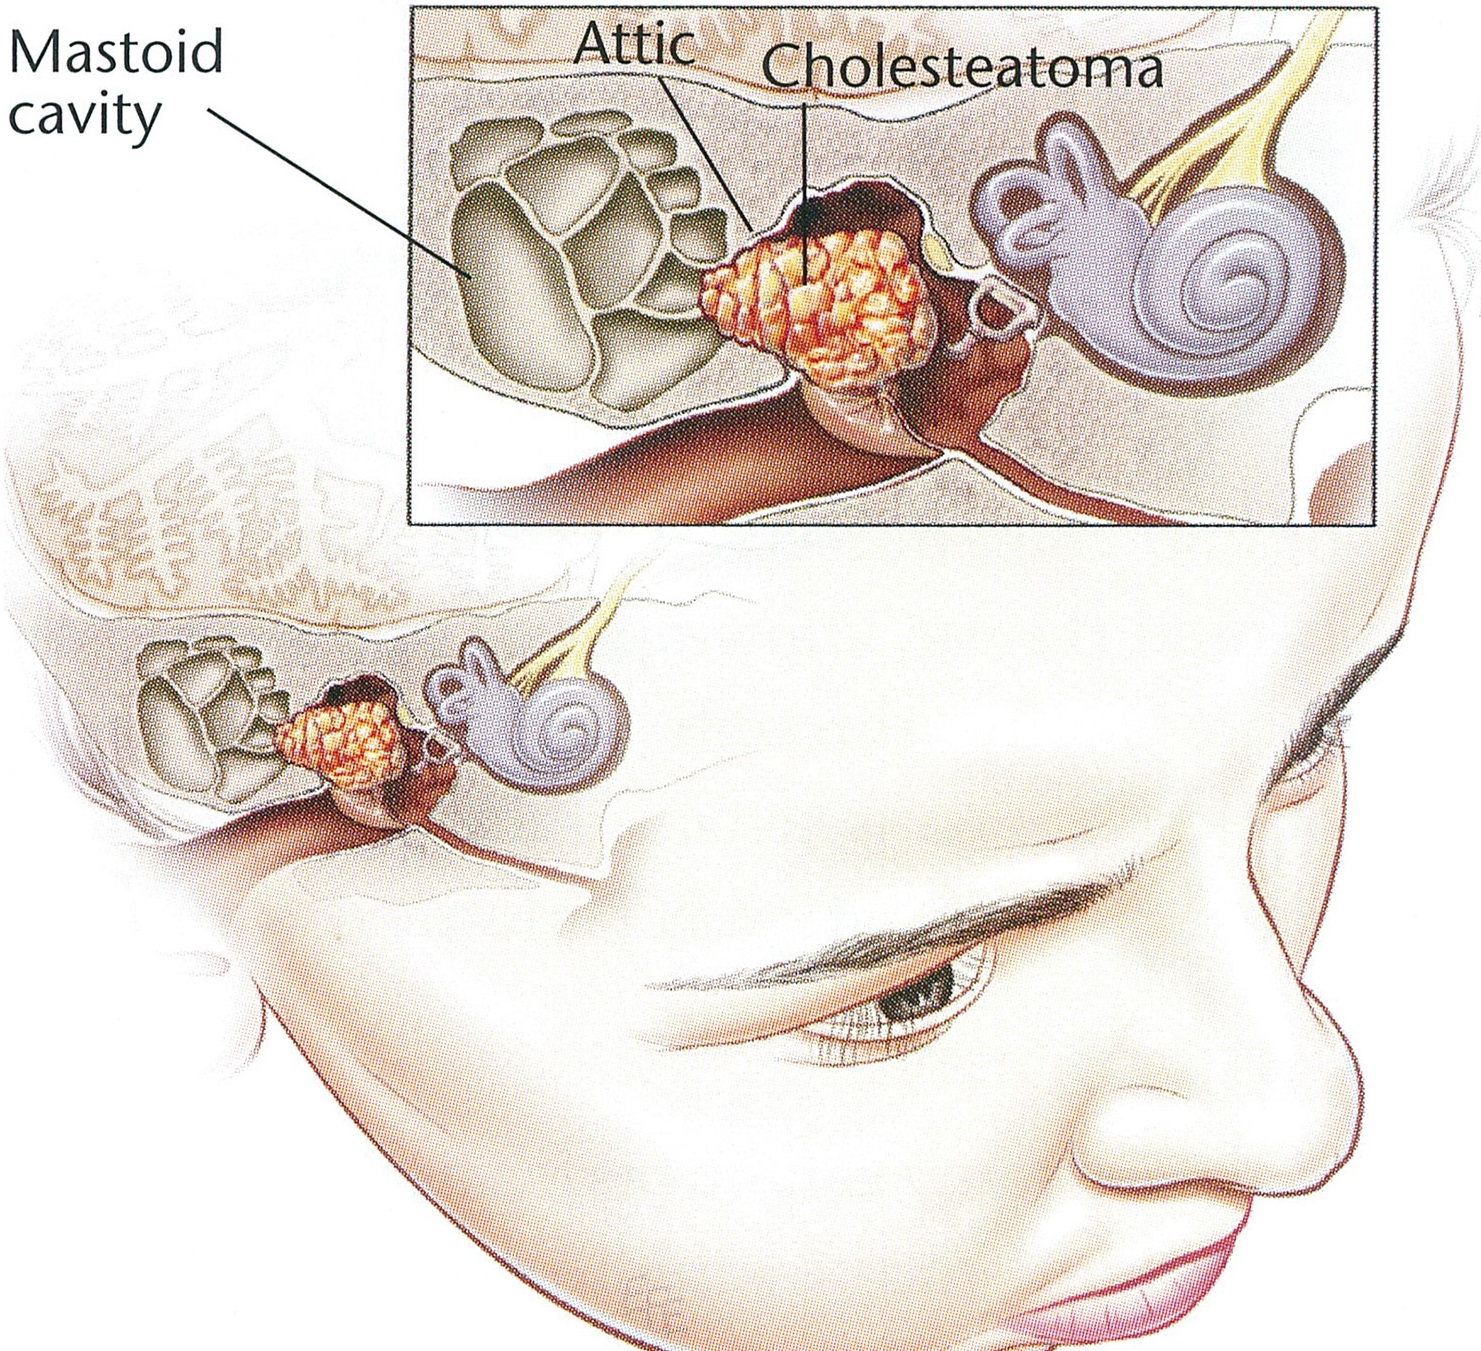

Overview

Package includes:

Days in hospital : 3 to 4 Days (For patient and one attendant)

Days in hotel : 7 Days (For patient and one attendant)

Room type in hospital : Shared

Room type in hotel : Private

Hotel category: Standard

Value added benefits of the Mastoidectomy and Tympanoplasty Including Meatoplasty: